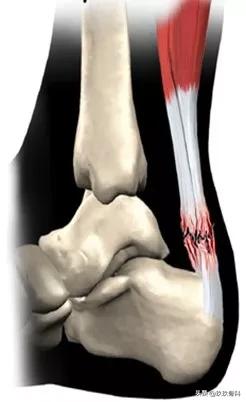

解剖

人体最长、最强壮的肌腱,起于腓肠肌和比目鱼肌,止于跟骨结节,长约 15cm,功能:踝关节跖屈,完成脚尖站立、正常走路、跑、跳、上下楼梯等动作。

断裂容易发生于偶尔参加运动的中年人,所以也称这类人为“周末运动员”,踝在过伸位突然用力,断裂多发生在跟腱止点上方2~6cm。

- 跟腱自上而下逐渐变窄增厚,跟骨结节上方2~6cm最窄,此处最薄弱